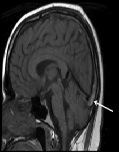

Acute Cerebral Venous Thrombosis with Papilledema and Complete Vision Loss

Dante Sorrentino, Anagha Medsinge*, Luis Gonzalez-Gonzalez, Gabrielle Bonhomme